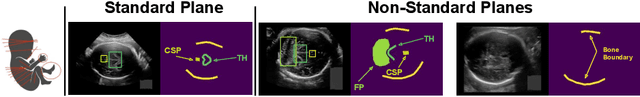

Abstract:Obstetric ultrasound image quality is crucial for accurate diagnosis and monitoring of fetal health. However, producing high-quality standard planes is difficult, influenced by the sonographer's expertise and factors like the maternal BMI or the fetus dynamics. In this work, we propose using diffusion-based counterfactual explainable AI to generate realistic high-quality standard planes from low-quality non-standard ones. Through quantitative and qualitative evaluation, we demonstrate the effectiveness of our method in producing plausible counterfactuals of increased quality. This shows future promise both for enhancing training of clinicians by providing visual feedback, as well as for improving image quality and, consequently, downstream diagnosis and monitoring.